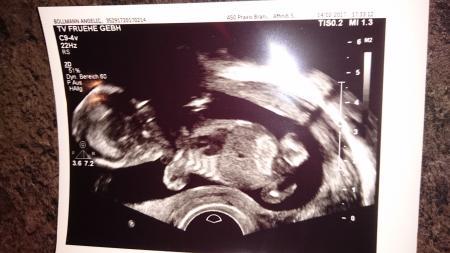

Hi Mädels Schaut euch doch mal bitte das Ultraschall Bild an und sagt was ihr meint :)

Bild zu outing - eure meinung - Forum für August - Mamis

Ich hab noch nie ein Outingbild gesehen, aber ich würde sagen Mädchen.

Also ich finde, es sieht aus wie ein Mädchen

Für mich auch Mädchen...

Mädchen :) Lg

Mädel würde ich auch sagen Und Mädels.... fangt nicht jetzt schon so an. Man liest es immer anders als wenn man es sich sagen würde also reagiert nicht gleich so allergisch aufeinander wenn etwas mal komisch klingt.

Also für mich sieht das eher danach aus, als wenn da das Kleine nach der Kamera greift Ich lass mich lieber doch nich zu einer Äußerung hinreißen. Ich hab aber auch keine Erfahrung, was Outtings oder überhaupt diese Bilder aussagen.